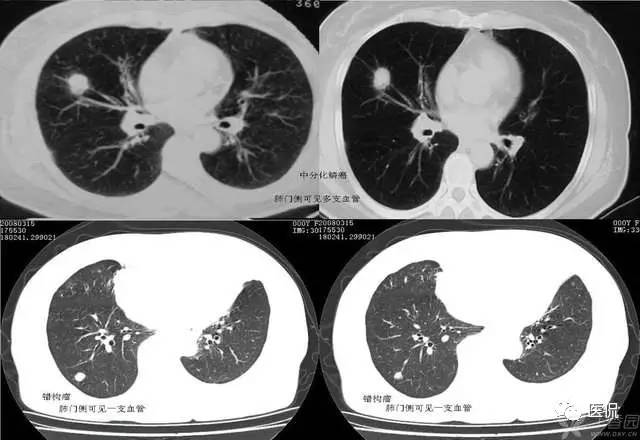

血管集束征的形成是由于肿瘤组织向血管支气管鞘或小叶间隔生长,瘤体内纤维组织增生或瘢痕形成,牵拉临近血管向瘤体集中所致。其中进肺门侧的血管束、支气管构成,血管壁多为扩张的小动脉,说明肺癌供血丰富;远肺门侧的血管束由扩张的小静脉组成,可能和静脉回流受阻有关。血管集束征的形成机制是由于恶性肿瘤细胞产生肿瘤生成因子诱发肿瘤形成新生血管,尤其是血供丰富的恶性肿瘤,由于其生长活跃,常致使肿瘤供血的血管代偿性增粗,这些血管长扩张或伴有肿瘤细胞的支气管动脉鞘浸润或瘤栓形成。这就意味着,肿瘤或结节周围血管是否增粗表明该病变的良恶性程度。血管集束征的出现与肿瘤或结节的大小有关,小于1公分的病灶较少出现;腺癌出现的的几率较高,因为腺癌供血丰富,纤维化形成的更明显。尤其要注意的是,一支血管引向结节或肿瘤内,不只仅见于恶性结节,也可见于良性病变如结核球、炎性假瘤或错构瘤。对于引向两性结节的这支血管可看作血管连接,而不是血管集束征。多支血管引向病变即出现了血管集束征这在恶性肿瘤出现的机会较高。此外,肺恶性结节累计静脉的机会更多,病灶不论大小,如果见到结节累及静脉,强烈提示恶性可能。判断某支血管是动脉还是静脉,主要根据其走形来判断,动脉主要和支气管伴行,静脉主要位于病灶的边缘绕行。关于血管集束征的血管,有学者认为大多数并非肿瘤供血血管或肿瘤血管,被肺癌卷入的肺动脉不参与肿瘤供血。另外,肺癌瘢痕的形成和癌巢的增殖与破坏与血管集束征和胸膜凹陷征的形成有关。血管集束征主要见于肺癌,尤其是腺癌和肺泡细胞癌。但是该征像不仅见于恶性肺结节,肺良性病变如结核球、球形肺炎等也可见到。所以仅根据血管集束征判断病变的良恶性并不是完全可靠的。

腺癌粗大的引流血管: